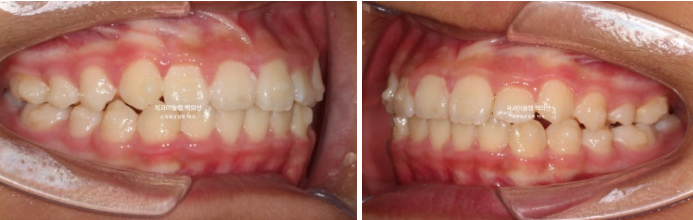

악궁확장을 통한 덧니 배열을 목표로 인비절라인 퍼스트 교정치료를 권유드렸습니다.

24년 2월부터 9월까지 첫세트의 19개 장치를 모두 낀 후 모습입니다.

24.09

중심선은 개선되었으나 약간의 불일치가 남아있으며 반대교합과 덧니는 모두 개선되었습니다.

그 사이 하나 남아있던 유치가 빠지고 완전한 영구치열에 접어들었습니다.

중심선 개선을 위해 추가장치 제작을 하기로 합니다.